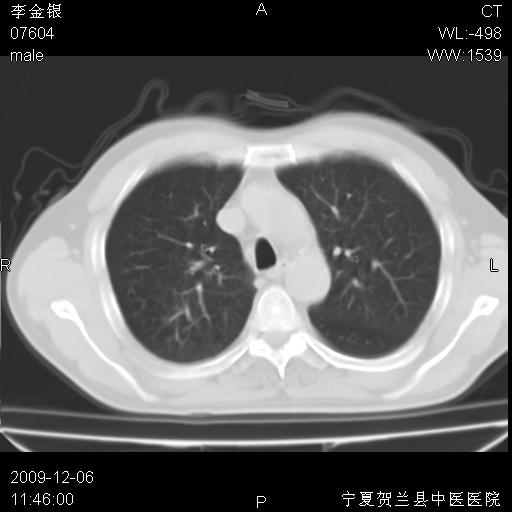

该病人 ,男,62岁,主因咳痰带血两天

考虑右肺中央型占位性病变并阻塞性肺炎.(右肺上叶支气管变窄),建议支纤镜检查.

支持右侧中央型肺癌伴上叶阻塞性炎症.

考虑右肺中心型肺癌伴阻塞性肺炎及右肺门淋巴结转移,建议纤维支气管镜进一步检查。

支气管壁明显增厚 管腔狭窄,腔静脉后多个淋巴肿大,结合年龄病史考虑右肺上叶中央型肺癌并阻塞性肺炎

右肺上叶后段支气管阻塞,右上肺门占位,相应肺段阻塞性肺炎,右肺门有淋巴结肿大。诊断右肺上叶中心型肺癌,阻塞性肺肺炎、右肺门淋巴结转移。

右上叶支气管狭窄,管壁增厚,远端斑片状软组织影,病灶邻近叶间裂,叶间裂无移位。

诊断右肺中央型肺癌。

那个片影应该大部分都是病灶,病灶沿肺段支气管分支生长,后段完全显示不清、闭塞。若为不张应该伴有叶裂的移位,若为炎症应有空气支气管征。